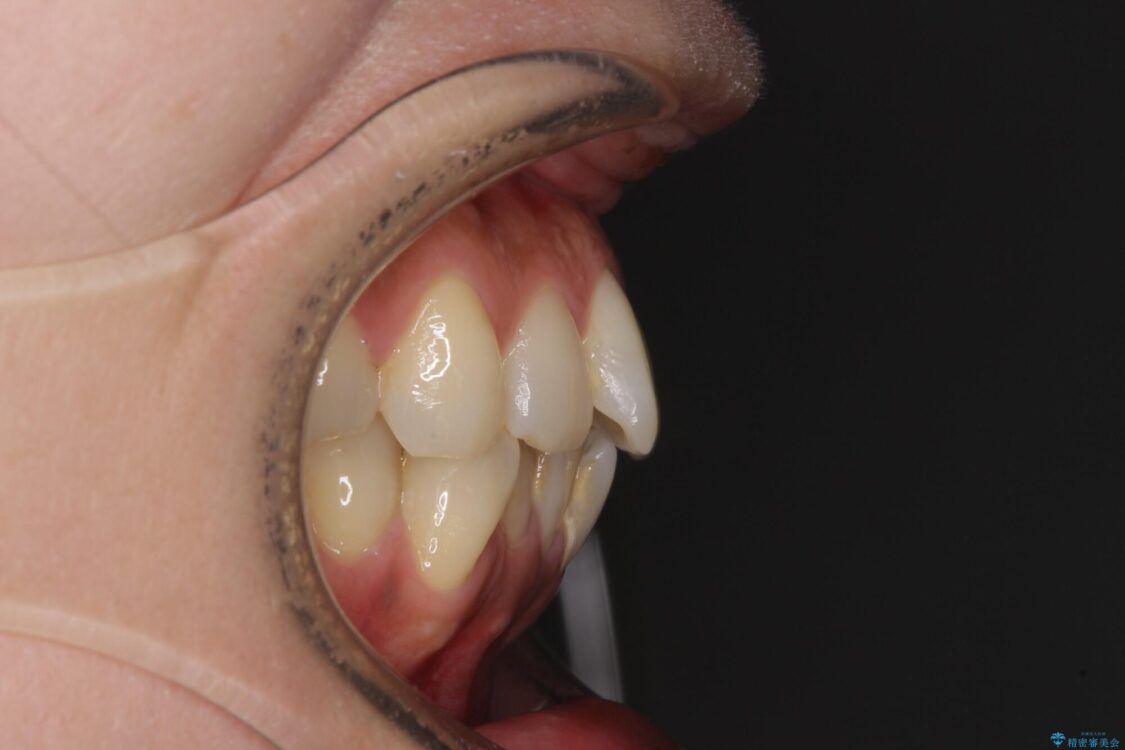

全体的なデコボコと、以前抜歯した歯のスペースを閉じた部分が気になるとのことで来院された患者様です。

左上第一大臼歯を抜歯した際に、スペースを閉じたそうですが、歯が傾斜してものが挟まって不快とのことでした。

治療前

• インビザラインによる矯正治療と奥歯のインプラント治療 治療前画像